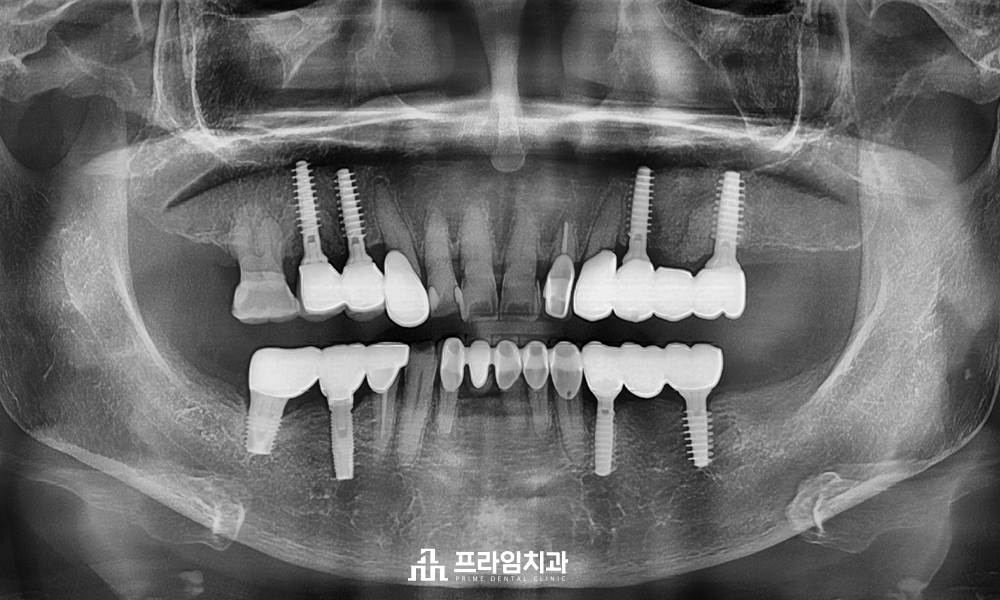

환.자분의 구강 상태를 충분히 고려하여

완산구임플란트 치과에서는

매직코어 최소침습 임플란트 수술의 장점을

설명한 뒤 진행하였습니다.

잇몸뼈가 많이 소실된 상태에서도

불리한 조건에도 불구하고,

절개 없이 안정적으로 임플란트 식립을

완료할 수 있었습니다.

개수가 많아 걱정하셨던

환.자분께서도 빠르고 편안한 치료 과정과

회복 속도에 대해 높은 만.족감을 표현하셨습니다.